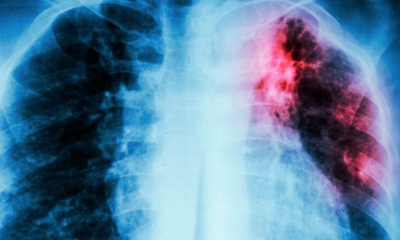

Cada 24 de marzo se conmemora el Día Mundial de la Tuberculosis, una oportunidad para visibilizar una enfermedad prevenible y tratable que aún representa un importante desafío...